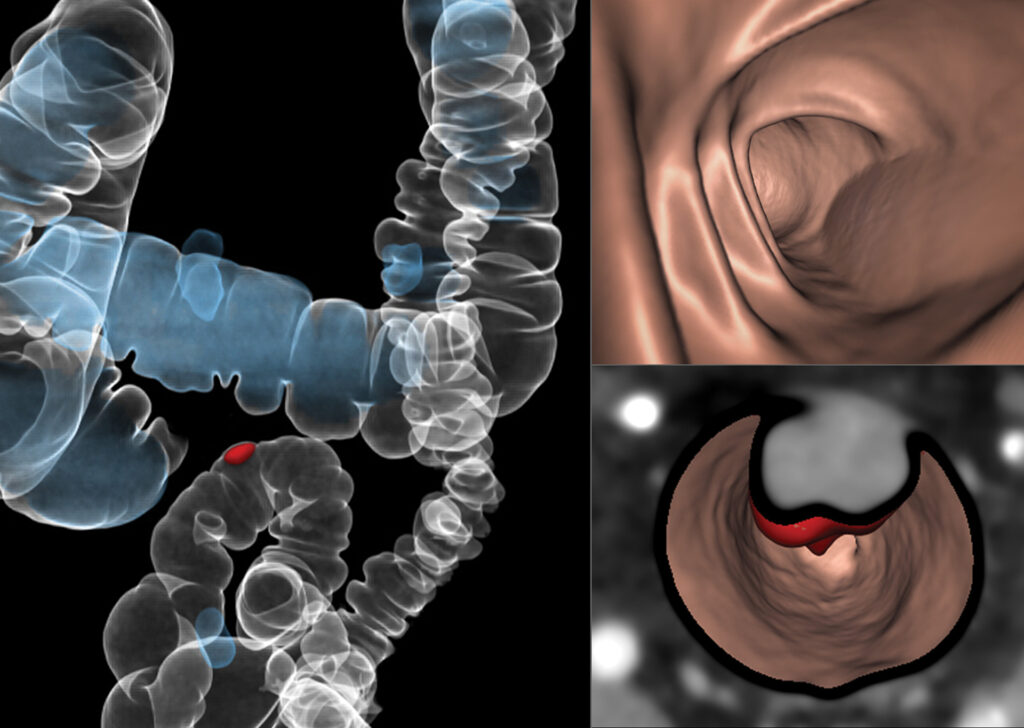

CT Colon Analysis

CT Colon Analysis provides clinicians with the ability to perform CT colonography. It provides optimized layouts for 2D and 3D examination of the lumen, including tools for quantitative analysis of suspected polyps.

iCAD VeraLook® CT Colon CAD

iCAD VeraLook CT Colon CAD uses sophisticated image processing software to identify colon polyps in CTC images, which can help to streamline the reading process and improve workflow for radiologists while supporting greater accuracy, consistency.